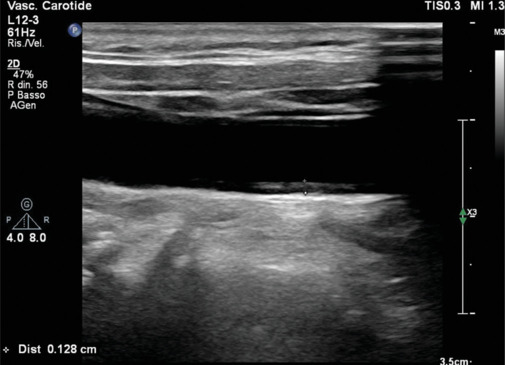

心血管疾病(cvd)仍然是世界范围内发病率和死亡率的主要原因,传统的预防措施侧重于改变生活方式、药物干预和风险分层。最近,成像已经成为心血管预防的一种有趣的工具。这篇综述探讨了各种成像方式在早期发现、风险评估和疾病监测中的作用。无创技术,如颈动脉超声、动脉硬度评估、超声心动图和冠状动脉钙评分,可以识别亚临床动脉粥样硬化和心室功能障碍,提供补充传统危险因素的见解。冠状动脉计算机断层血管造影和心脏磁共振提供血管和心肌病理的高分辨率可视化,有助于精确的风险分层。此外,心外膜脂肪组织和肝脂肪变性等新兴标志物正逐渐被认为是心血管风险的潜在预测因素。人工智能(AI)的进步通过增强图像解释、自动化风险预测和促进个性化医疗,正在彻底改变心血管成像。未来的研究应侧重于优化影像学与临床工作流程的整合,改进风险预测模型,探索人工智能驱动的创新。通过利用成像技术,临床医生可以加强一级和二级预防策略,最终减轻心血管疾病的全球负担。

Cardiovascular diseases (CVDs) remain the leading cause of morbidity and mortality worldwide, and traditional preventive measures focus on lifestyle modifications, pharmacologic interventions, and risk stratification. Recently, imaging has emerged as an interesting tool in cardiovascular prevention. This review explores the role of various imaging modalities in early detection, risk assessment, and disease monitoring. Noninvasive techniques such as carotid ultrasound, arterial stiffness assessment, echocardiography, and coronary artery calcium scoring enable the identification of subclinical atherosclerosis and ventricular dysfunction, providing insights that complement conventional risk factors. Coronary computed tomography angiography and cardiac magnetic resonance offer high-resolution visualization of vascular and myocardial pathology, contributing to refined risk stratification. Furthermore, emerging markers such as epicardial adipose tissue and hepatic steatosis are gaining recognition as potential predictors of cardiovascular risk. Advancements in artificial intelligence (AI) are revolutionizing cardiovascular imaging by enhancing image interpretation, automating risk prediction, and facilitating personalized medicine. Future research should focus on optimizing the integration of imaging into clinical workflows, improving risk prediction models, and exploring AI-driven innovations. By exploiting imaging technologies, clinicians could enhance primary and secondary prevention strategies, ultimately reducing the global burden of CVDs.